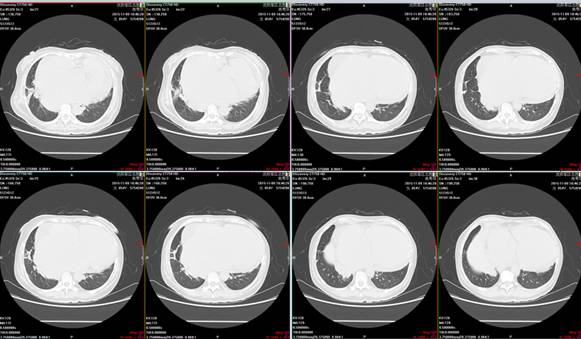

肺部CT示右肺下叶基底段见斑片状稍高密度,边界清晰。考虑:考虑右肺下叶炎症,不除外占位性病变。

(复查肺增强CT,炎症部分较前有所吸收,未发现肺部占位性病变)